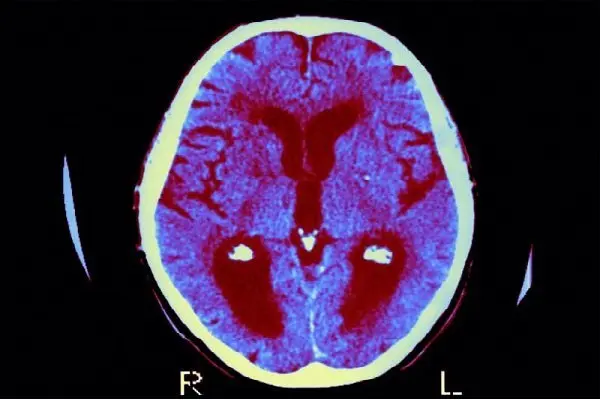

دارویی که برای مقابله با بیماری دیابت Diabetes نوع دوم به کار گرفته شده، قابلیت شگفت انگیز دیگری هم دارد و می توان از آن برای مقابله با کاهش حافظه و بهبود وضعیت مبتلایان به آلزایمر استفاده کرد.

به گزارش یاهونیوز، داروی یادشده می تواند اثرات خطرناک برخی بیماری های مربوط به اعصاب مغز را هم از بین ببرد.

محققان دانشگاه لنکستر انگلیس می گویند استفاده از این دارو نتایج بسیار امیدوارکننده ای داشته و باعث کاهش مرگ مولکول های یک نوع پروتئین حیاتی سلول های مغز شده است و این تحول می تواند منجر به یافتن یک روش درمانی جدید برای مقابله با بیماری زوال عقل شود.